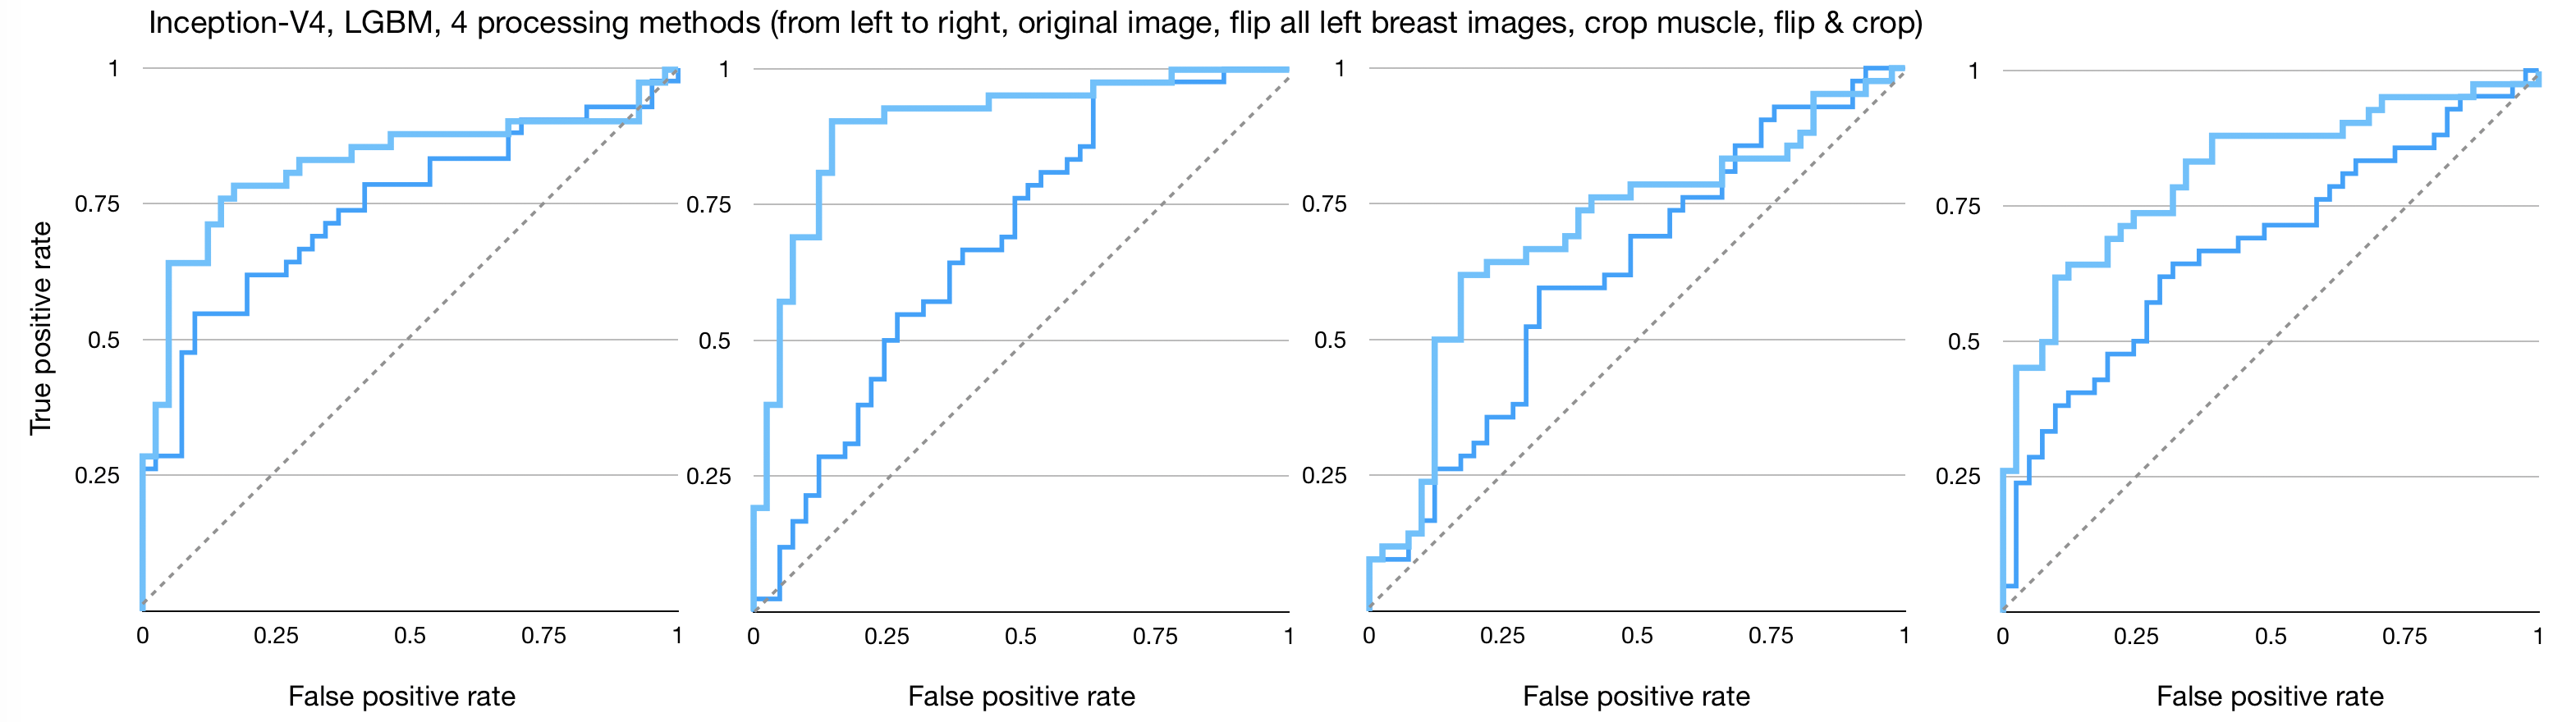

Figures 4, 5, and 6 show the imaging for which both humans and CNNs make mistakes, model introduced errors, and model corrected human errors. Figure 7 shows the receiver operating characteristic curve (ROC curve) for each of the 16 end-to-end models between the CNNs and radiologist gist plus CNNs. Tables 1 and 2 show the AUC data and differences used in the main text from the 16 conditions we have tested. Although the present work provides knowledge about adding radiologists’ data into CNN, it does not allow for training on new data, thus restricting our application domain to a small range of in-house data.